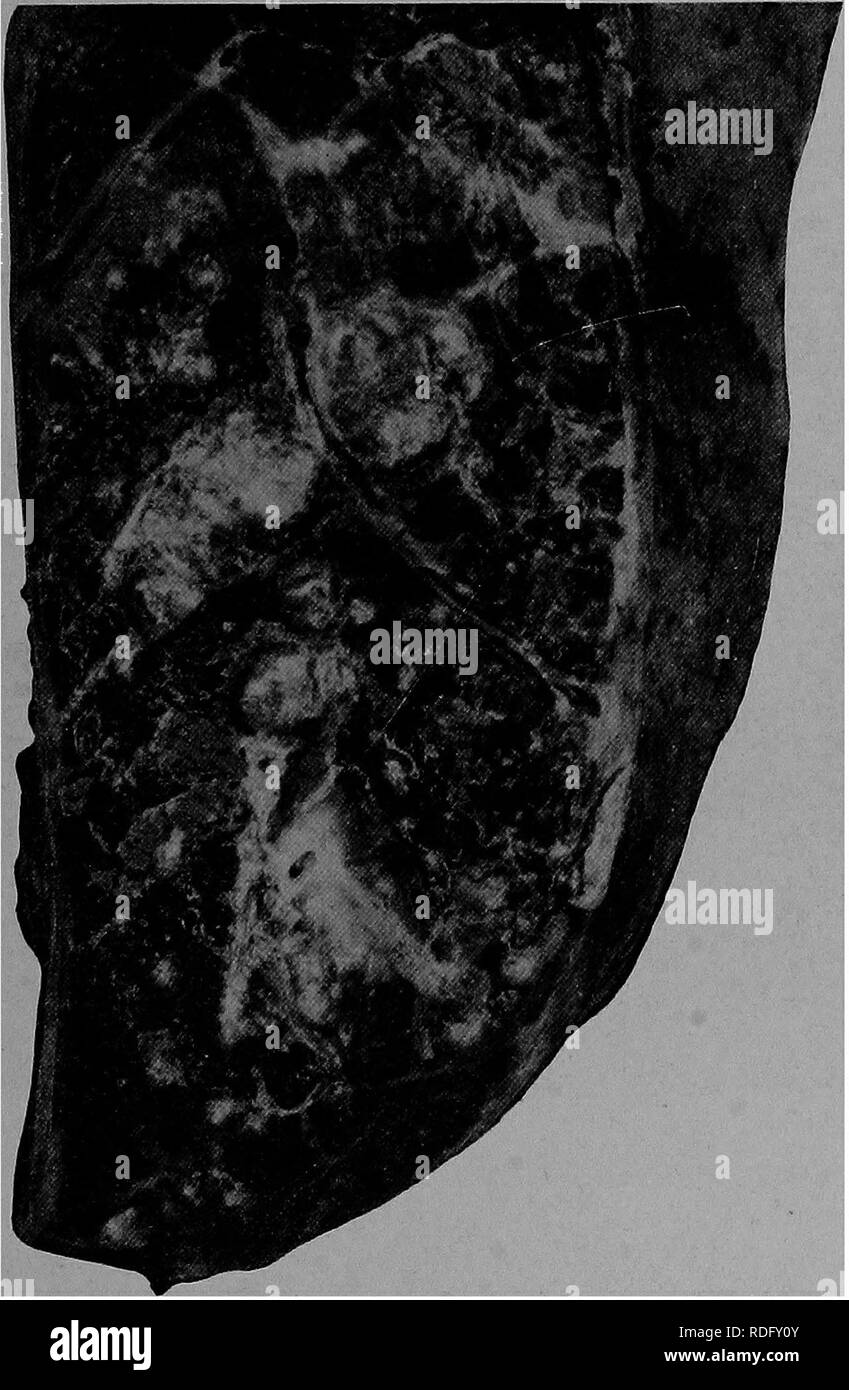

Figure 1 from MORPHOLOGICAL FINDINGS IN LUNGS OF THE HORSES WITH Inflammatory Lung Disease In Horses Fever and abnormal lung sounds are rare. Inflammatory airway disease (iad) is also described as mild to moderate equine asthma. The cause is unclear, but viral respiratory infection,. Cough, poor performance and excess mucus within the airways on endoscopy is characteristic of iad. Any respiratory dysfunction can cause a decline in ventilation and gas exchange. Iad is a respiratory disease. Inflammatory Lung Disease In Horses.

A) Gross photograph of the lungs from a horse with Klebsiella Inflammatory Lung Disease In Horses The cause is unclear, but viral respiratory infection,. Inflammatory airway disease is characterized by excessive mucus in the airways and poor exercise performance in young horses. Any respiratory dysfunction can cause a decline in ventilation and gas exchange. Affected horses appear normal at rest; Fever and abnormal lung sounds are rare. Chronic, nonseptic inflammatory disease of the lower airways is. Inflammatory Lung Disease In Horses.